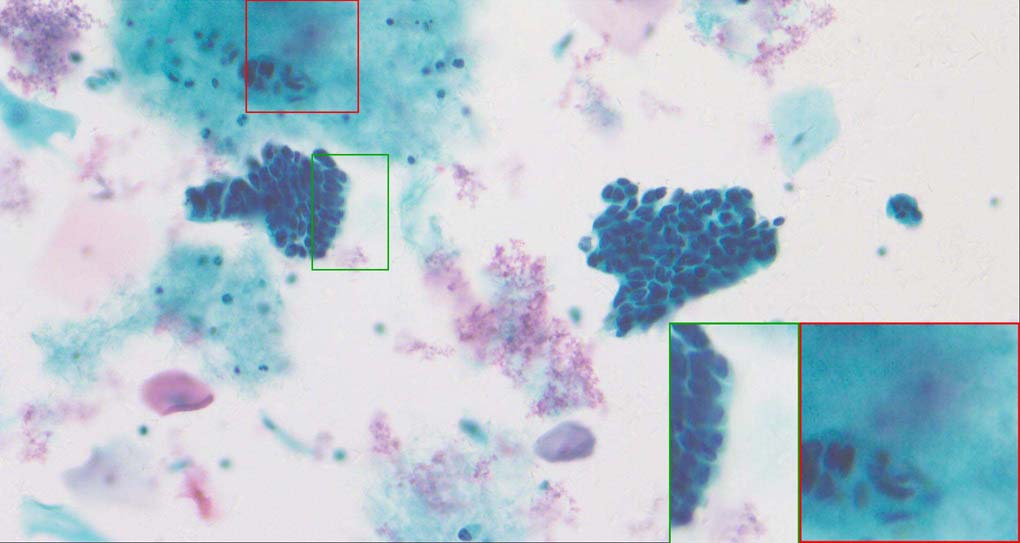

A good image fusion method should contain the following properties. First, it preserves both the details of small size objects and the integrity information of large size objects in the fused image, even in the case of the size of the interested objects varying largely in the image. For example, the cervical cell images from the microscope contain both small size isolated cells and large size agglomerates, which are both useful for cervical cytology [5]. Second, it should be efficient enough to handle large-scale data. For instance, it needs to process thousands of fields of view (FoV) in an acceptable time for the whole slide scanning in digital cytopathology [6], which requires to fuse a series of high resolution images captured at each FoV in a very efficient way. Third, it does not produce obvious artifacts. Despite being studied extensively, to our best knowledge, existing fusion methods may not meet these requirements simultaneously.

To demonstrate the effectiveness and efficiency of the proposed image fusion method , we conduct a set of comparative experiments on three image datasets. The first is composed by 8 pairs of multi-modal medical images and the second one contains 15 pairs of multi-focus gray or color natural images. These two datasets are often used in many related papers and some examples are shown in Figure 3(a) and Figure 3(b). The third one is a new multi-focus cervical cell image dataset collected by ourselves, which consists of 15 groups of color images and each group contains a series of multi-focus cervix cell images with size of or , etc. Some source examples are shown in Figure 3(c). Our source code implemented in C++ along with the new multi-focus cervical cell image dataset is available online.

Similarly, as shown in the close-up views of Figure 10, the fused images from DSIFT, IM, MWGF and BF are blurred and lose some nucleus details, while the results from DTCWT, GFF, CNN and NSCT produce halo artifacts. LP-SR based method can keep details well but also produces halo artifacts and other noise. Our method can preserve the focused areas of different source images well without introducing any artifacts. For the example illustrated in Figure 11, the fused images generated by DSIFT, DTCWT, IM and NSCT all fail to preserve the focused areas of different source images and result in extremely blurred images. The GFF, CNN, MWGF and BF based method introduces a lot of color distortion of the nucleus regions and the obvious halo artifact. The result of LP-SR based method is close to the one of our method but introduces some odd color distortion. Again, our method produces fused image which can preserve the focused areas of different source images well without introducing any artifacts.